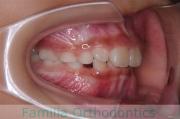

No.16V-139

- 叢生

- 16歳

- 男性

下の前歯が後ろにあるのが気になるとのことで来院されました。非抜歯で行うことも可能でしたが、上下左右から小臼歯抜歯をして治療を行うことをご希望になりました。

マルチブラケット法にて治療を行い、約3年、40回の通院が要でした。

かみ合わせが深い(上の前歯で下の前歯が覆われてしまう)ので、保定をしっかりしないと、また深くなってきてしまいやすいです。